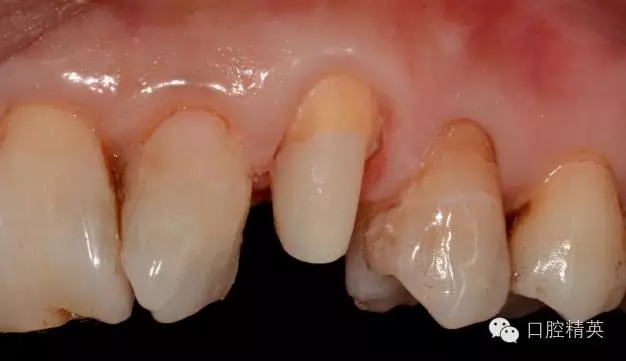

圖1 23口內(nèi)修復(fù)前情況:殘根位于齦上3MM,牙周無紅腫.

圖5 置纖維樁樹脂樁備牙后情況